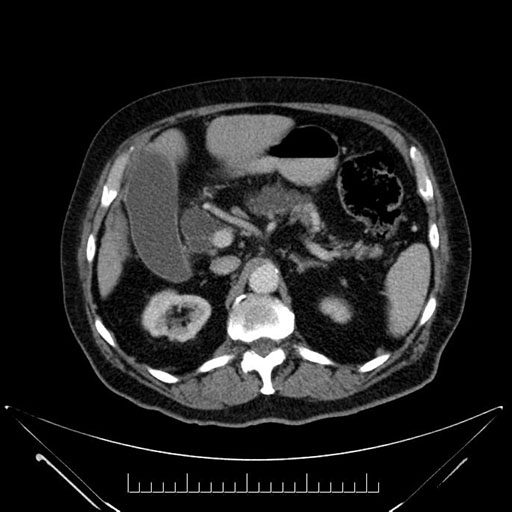

Whipple (pancreaticoduodenectomy) [case 7]

Imaging Analysis

Look through the patient's CT scan to identify any areas of concern for the necessary procedure.

Axial - stented